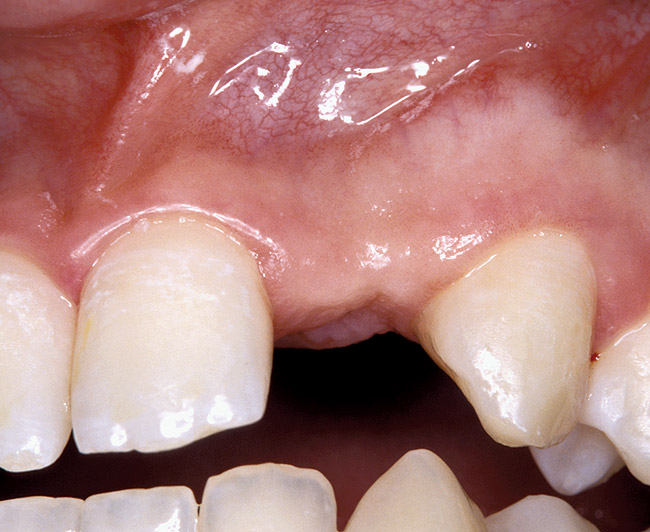

Figure 3  DIAGNOSTIC INFORMATION A difference in clinical appearance of the left lateral, buccal view.

Figure 3

Periapical radiographs were taken to help determine the mesial-distal inclinations of the adjacent tooth roots (Figure 1). The radiographs revealed a serious issue, convergent roots for the right canine and right central, which eliminated that area as a potential implant-receptor site. The space between the left central and canine teeth was minimal, although the roots were relatively parallel. Clinical examination (manual palpation of the root eminences superiorly to the vestibule on the right side) confirmed the root convergence (Figure 2). The flat, wide zone of the keratinized tissue and lack of interdental papilla was evident for the missing right lateral incisor. There was a marked difference in clinical appearance for the left lateral, which could impact the eventual plan of treatment (Figure 3). Other significant clinical findings included bilateral facial bone concavities, which existed as a result of the congenitally missing tooth roots. As a diagnostic cue to the underlying bone topography, it is important to follow the demarcation between attached and unattached gingival tissue, and note the crestal width of the available keratinized tissue (Figure 4).